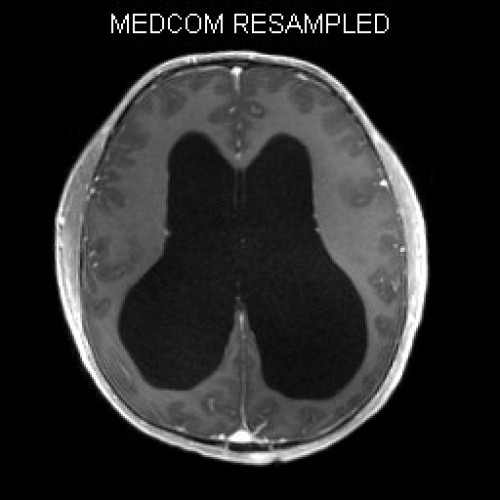

ICD: C75.3

ICD: G91.9

12-jähriger Junge. Die Eltern werden zu einem Gespräch bei der Klassenlehrerin gebeten, weil ihr Sohn sehr unaufmerksam geworden sei und seine Leistungen in der Schule bedenklich abgenommen hätten. Er droht das Klassenziel der 6. Klasse nicht zu erreichen.

Den Eltern war seit längerer Zeit bereits aufgefallen, dass sich ihr Sohn nach der Schule am liebsten ins Bett lege, um für eine Stunde einen Mittagsschlaf zu halten.